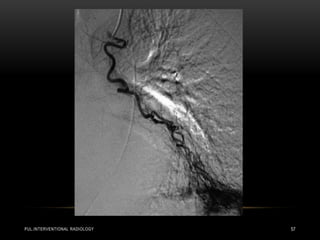

PUL.INTERVENTIONAL RADIOLOGY 57

PERCUTANEOUS TRANSCATHETER EMBOLIZATION PUL.INTERVENTIONAL RADIOLOGY49 • Recanalization and collateralization of the post-embolization PAVM can present in the range of 5% to 20%. • No device appears to be superior in preventing recanalization. • Study of 28 PAVMs showed that recanalization did not develop between 6 and 40 months in patients treated with AVP and coils.